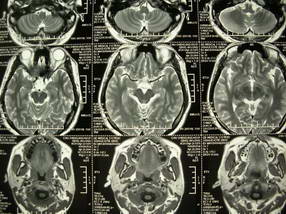

男、30、发现鼻咽部肿瘤侵犯海绵窦,未发现明显淋巴肿。请问国内那家医院治疗鼻咽部肿瘤最好?手术以何种方式为主?病灶可否全部切除?急切期待的大家的帮助。

扫描示鼻咽腔不对称,中度狭窄,右侧咽隐窝消失,局部软组织肿块,鼻咽右侧壁增厚形成肿块,突入鼻咽腔,肿块平扫呈等密度,肿块向深部侵润,右侧翼内外肌受侵,右侧咽旁间隙变窄;向后生长,头长肌界线欠清,向后上生长侵犯同侧颈动脉鞘区。双侧海绵窦增宽,内见软组织影与鼻咽部肿块相连。考虑鼻咽癌。鼻咽癌主要是放射治疗,且效果较好;到当地有治疗设备较大医院治疗即可。

这个病例有点特殊,和常见的鼻咽癌不太一样,以向颅内侵犯为主,骨质破坏区小。鼻咽癌首先要考虑,有没有其他可能?本人不会看mr片,期待有人能讲解,期待病理。